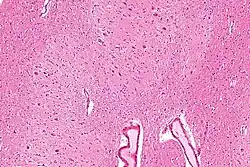

Micrograph of the dentate nucleus (pale pink). H&E stain.

The architecture of cerebellum is a repeating fractal, so a slice anywhere in the cerebellum gives consistent neuronal branching patterns. The eight cerebellar nuclei, located within the deep white matter of each cerebellar hemisphere, are grouped into pairs, with one of each pair in each of the two hemispheres. As a chunk of tissue, the dentate nucleus with overlying cerebellar cortex makes up a functional unit called the cerebrocerebellum. Thus, there is a part of cerebellum that communicates exclusively with the dentate nucleus.[4]